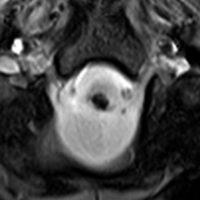

3歳の髄芽腫です。発症時から小脳表面や小脳橋角部を含めて転移がありました stage M2。化学療法で腫瘍はかなり縮小して,3歳7ヶ月まで頑張ってから,後頭窩照射 25.2グレイ14分割と脳脊髄照射 CSI 28.8グレイ16分割の放射線治療をしました。当時このような例では,脳脊髄照射 36グレイが標準治療でしたから,これでもかなり線量を落としました。

左側の画像は照射後4ヶ月目です。延髄の左側に放射線壊死が生じました。これは数ヶ月かかってゆっくり消褪しました。右側の画像は照射後1年くらいのものです。大脳白質にびまん性に萎縮性変化がみられます。典型的な放射線治療による白質萎縮です。この程度の線量でも脳壊死や全脳萎縮を生じない子どももいます。